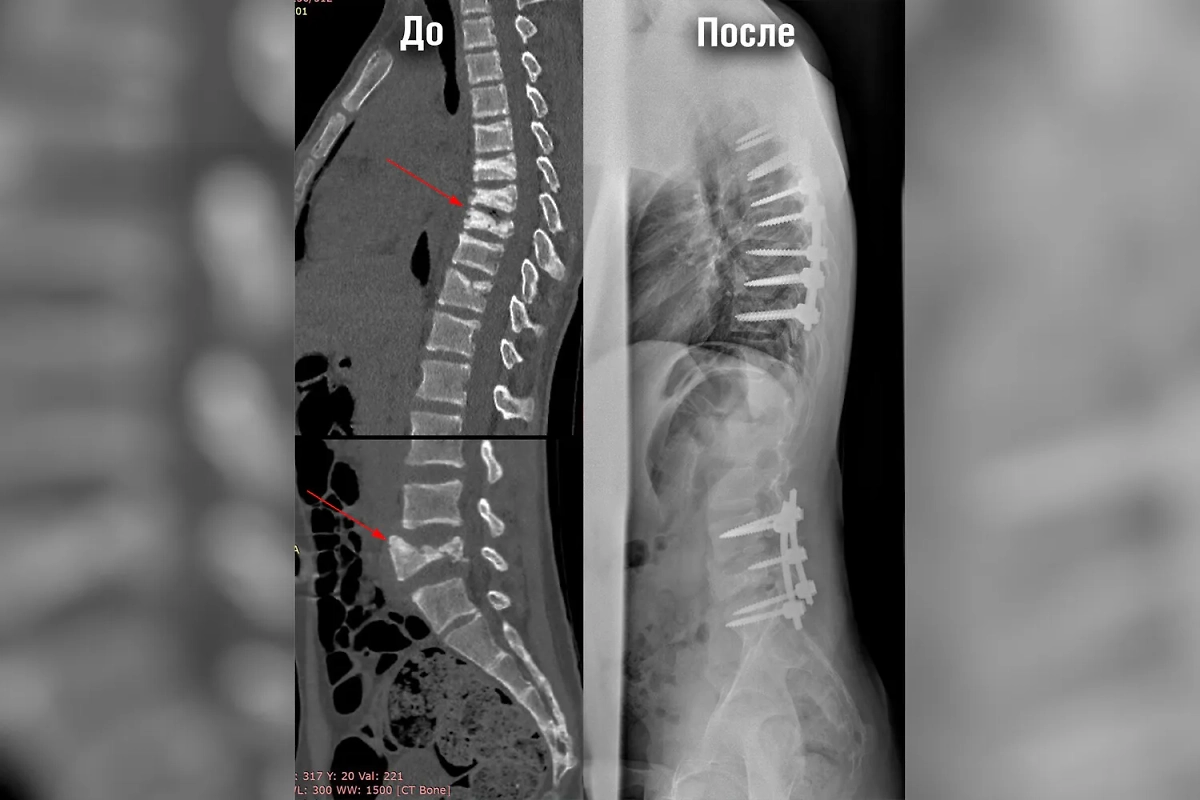

Хирург-вертебролог отделения травматологии и ортопедии РДКБ Андрей Пантелеев пояснил, что медики столкнулись с очень редким случаем, а настолько тяжёлые переломы в нескольких отделах позвоночника ранее не были описаны в профильной литературе. Однако свою работу врачи выполнили профессионально.

Настоящее чудо сотворили сотрудники Российской детской клинической больницы Минздрава РФ. Они успешно прооперировали позвоночник 15-летнего пациента, пострадавшего во время тяжёлого приступа эпилепсии. Врачи не только спасли ребёнка от утраты двигательных функций конечностей, но и значительно улучшили качество его жизни, назначив необходимую лекарственную терапию.

«Постоянные тяжёлые приступы, которые сгибали ребёнка пополам, угрожали смещением сломанных позвонков и сдавлением спинного мозга, что могло привести к потере двигательных функций конечностей и другим тяжёлым неврологическим нарушениям», — отметила специалист.